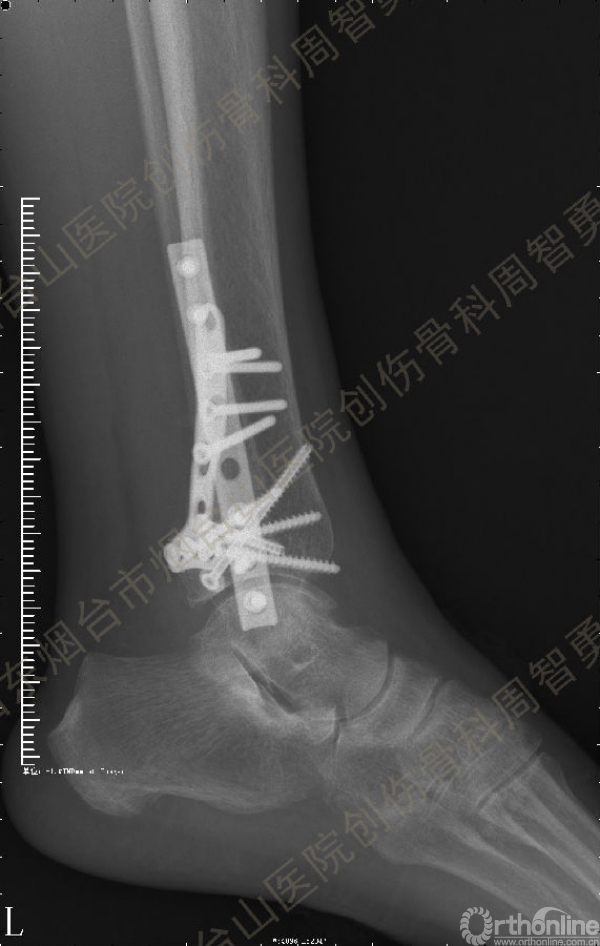

患者取俯卧位,轻度屈膝,小腿下垫枕使足离开床面。取长约10cm的踝关节后外侧切口,皮肤切口位于外踝后缘与跟腱的中线,远侧延伸至外踝尖。皮下与深筋膜间显露、保护小隐静脉和腓肠神经,纵向切开腓骨肌浅面深筋膜,显露腓骨肌腱。将腓骨肌腱牵向外侧显露后浅室和后深室间隔,透过肌间隔可见踇长屈肌。切开肌间隔显露踇长屈肌并向内侧牵开,显露胫骨远端后侧骨折块。保护腓动脉、下胫腓后韧带和骨折块上的骨膜。在后内侧骨折块和后外侧骨折块中间的骨折线切开骨膜并骨膜下游离数毫米,分别以胫后肌腱腱鞘和下胫腓后韧带为铰链,将后内侧骨折块和后外侧骨折块翻向内侧和外侧。显露后内侧骨折块腹侧向近端塌陷的骨软骨骨折块。见后内侧骨折块腹侧有约4.0 mm×3.0 mm×3.0 mm大小向近端塌陷的骨软骨骨折块,给予切除。取长约5cm的踝关节后内侧入路,切开皮肤皮下并适当向两侧游离,不切开屈肌支持带,仅切开后内侧骨折块内侧缘和近侧缘的骨膜。通过后外侧入路和后内侧入路显露后内侧骨折块的外侧缘、近侧缘和内侧缘,直视下解剖复位后,2.0 mm克氏针临时固定。直视下解剖复位后外侧骨折块,并用2.0 mm克氏针临时固定。返回后外侧切口,向外侧游离皮瓣,内牵腓骨长短肌腱显露外踝骨折,解剖复位后用2.0 mm克氏针临时固定。术中透视显示骨折块解剖复位。一枚4.0mm空心螺钉固定于后内侧骨折块的内上缘,另一枚4.0mm空心螺钉固定于后丘,5孔桡骨远端T型接骨板抗滑固定于后内侧骨折块和后外侧骨折块。8孔1/3管状板固定外踝骨折。术中Cotton试验阳性,复位下胫腓联合后,1枚3.5mm皮质骨螺钉固定。Chaput骨折块未作处理。术中及术后X线摄片示骨折解剖复位,内固定物位置正确。术后,踝关节于背伸0~5°,短腿石膏后托或支具固定2周。2周去除外固定开始踝关节主动功能练习。术后8周,X线片示骨折解剖复位,骨折线模糊,内固定物在位(图3a,b)。术后第11周开始部分负重,第13周拔除固定下胫腓联合的螺丝钉,逐步开始完全负重。术后4个月复查:X线片示骨折解剖复位,骨折线消失,内固定物在位;左侧踝关节主动背伸较健侧差10°,跖屈差10°;踝关节无疼痛,肌力较健侧无明显减退。

↑ 图 3a

↑ 图 3b

图 3 术后8周X线片示骨折解剖复位,骨折线模糊,内固定物在位